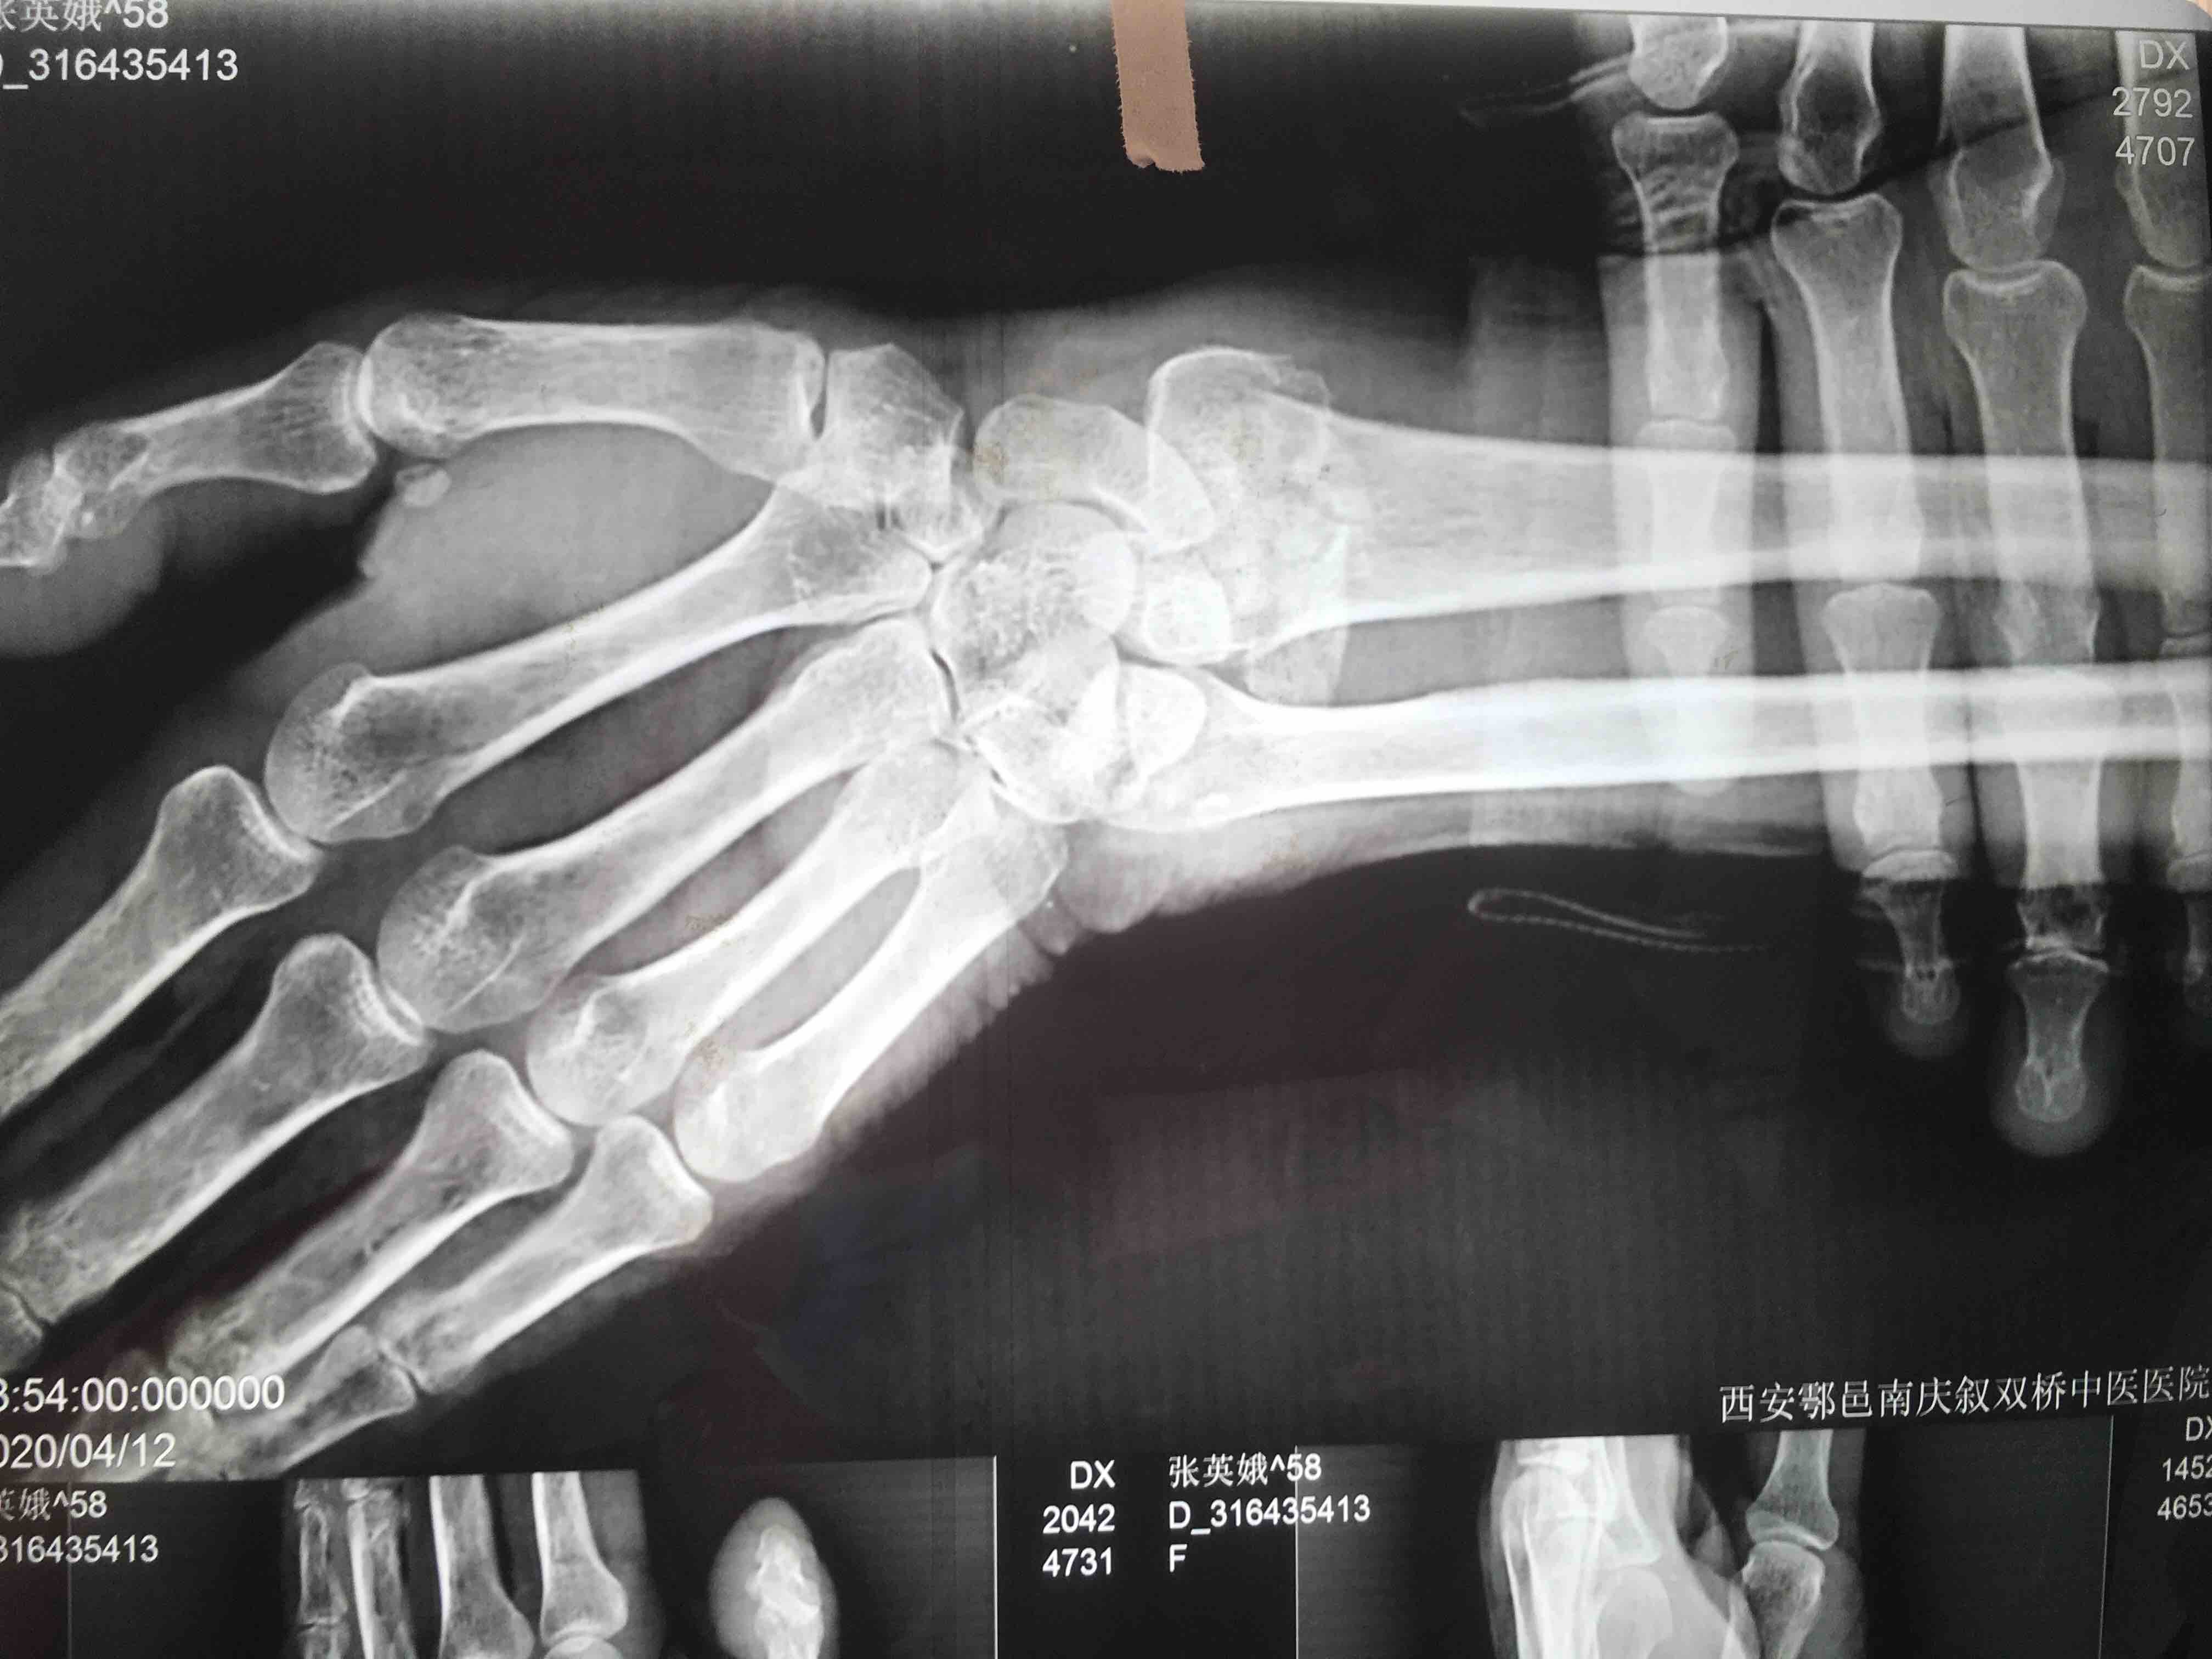

生命体征平稳,心肺复未见异常。左腕部肿胀明显,局部皮色皮温正常,畸形,压痛及纵向叩击痛阳性,腕关节活动受限,感觉血运正常。

诊断左colles骨折

在臂丛下行切复内固定术,术后抗炎消肿等处理。